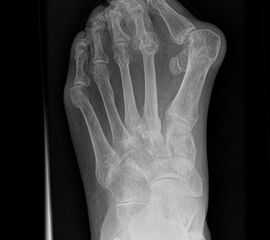

Fuß dp (dorsoplantar) mit Belastung

Positionierung:

• Der Patient steht unter gleichmäßiger Gewichtsbelastung auf beiden Füßen.

• Die Fußachse ist nach vorne gerichtet.

• Die Kassette liegt unter dem zu röntgenden Fuß.

• Der Zentralstrahl wird auf das Tarsometatarsalgelenk II zentriert.

• Die Röntgenröhre ist 15° vertikal gekippt.

• Anmerkung: Technisch lässt sich die Röhre beim stehenden Patienten nicht in 0° über dem Fuß positionieren. Eine Kippung der Röhre um 15° erlaubt darüber hinaus eine bessere Einsicht in die tarsometatarsalen Gelenke.

Kennzeichen des Röntgenbildes:

• Standardabbildung des Fußes zusammen mit der belasteten seitlichen Aufnahme und der unbelasteten Schrägaufnahme.

• Die belasteten Aufnahmen liefern relevante Informationen zur Fußstatik und sind die Grundlage aller achskorrigierenden Eingriffe an Vor- und Rückfuß.

• Sämtliche Winkelbestimmungen beziehen sich auf belastete Aufnahmen.

Besondere Bemerkungen zum Beispielbild:

• Schwere Hallux valgus Deformität.

• Die Sesambeine sind luxiert, ebenso das Großzehengrundgelenk. Luxation des Metatarsophalangealgelenks II.

• Degenerative Veränderungen der tarsometatarsalen (TMT) Gelenkreihe, betont TMT II und III.